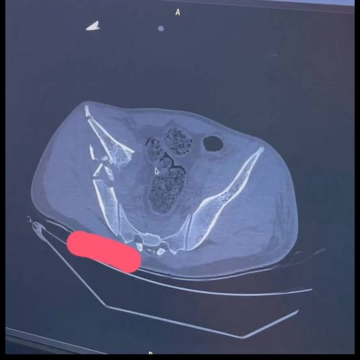

💊 33-летний мужчина поступил в травматологию с тяжелыми травмами: перелом таза с центральным вывихом бедра и раздроблением таза, а также перелом левого бедра.

👨‍⚕️ Сначала врачи стабилизировали конечности с помощью аппарата

внешней фиксации и закрепили бедро штифтом. Затем провели большую операцию и выполнили остеосинтез правой части таза - собрали кости «по кусочкам».